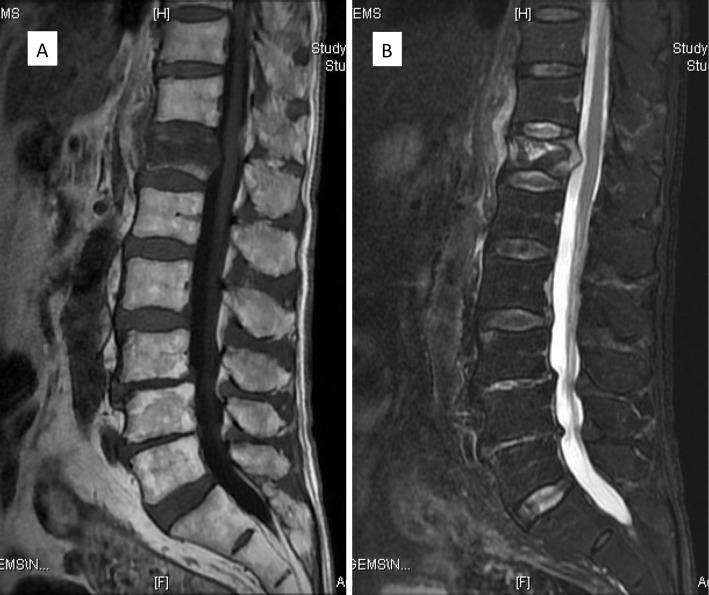

Methods: Surgical indications are a vertebral wedge angle difference of 10° or more, vertebral pedicle fractures, posterior wall fractures, and diffuse low-signal changes exceeding 50% on T1-weighted magnetic resonance imaging. The procedure is reserved for highly unstable cases following a comprehensive health assessment. The surgical technique involves prone positioning, fluoroscopy-guided percutaneous vertebral augmentation, and the use of downward PES in the cranial vertebral body and upward PES for the caudal vertebral body by percutaneous technique. The fixation range is one above and one below.

Abstract Image